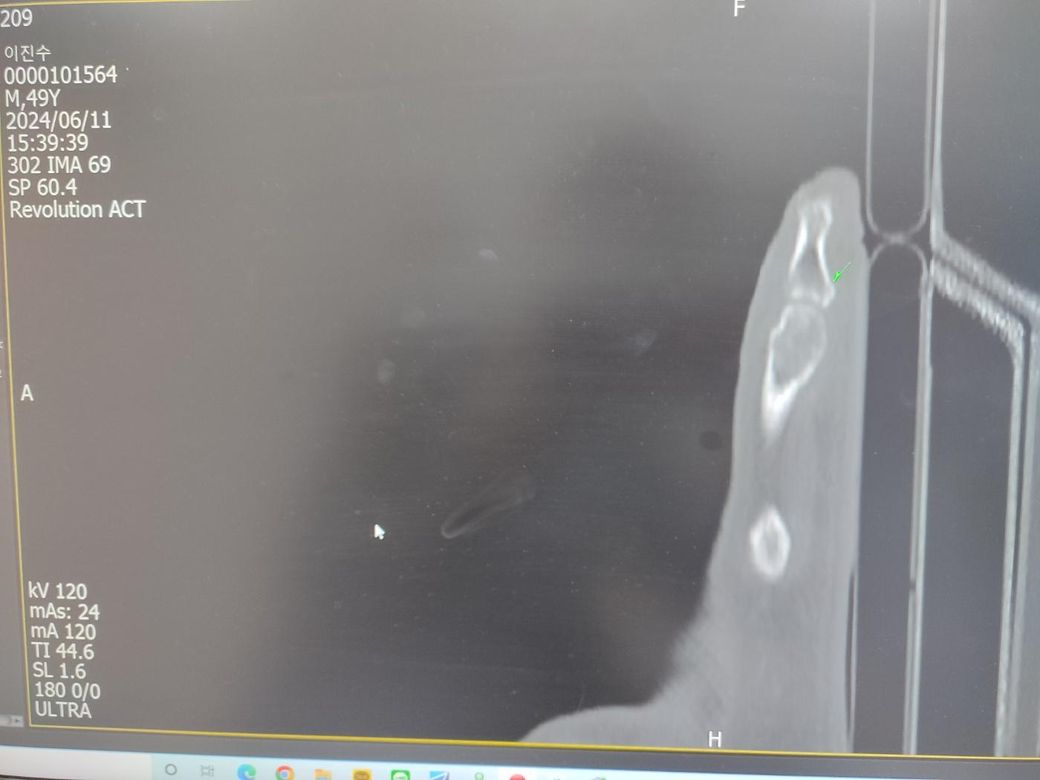

엑스레이만으로 판단미스로 두달만에 ct로 골절판정받았습니다.초반에 깁스없이 걷기운동 생활하고 스트레칭 운동하다가 통증이 안없어졌는데 지금은 걷는운동은전혀안하고 있는데 발가락을 뒤로젖히면 욱통증이옵니다.아직골절이 덜붙은거가요?언제쯤나을까요?ct첨부합니다.골절이 큰편인가요?

• 1번 째 사진

Ct상 골절이 확인됐다면 아직 골유합이 덜 된 상태일 수 있으며 뒤로 젖힐 때 통증은 회복 지연 신호일 수 있습니다.

초기 깁스 없이 움직인 것이 회복을 늦췄을 가능성이 있어요 완전 유합까지는 8~12주 이상 걸리기도 합니다. 지금은 안정 취하면서 정형외과에서 추가 고정 또는 물리치료 여부 상담받는 것이 좋아요!

골절이 CT로 관찰되었다면 큰 편은 아닙니다.